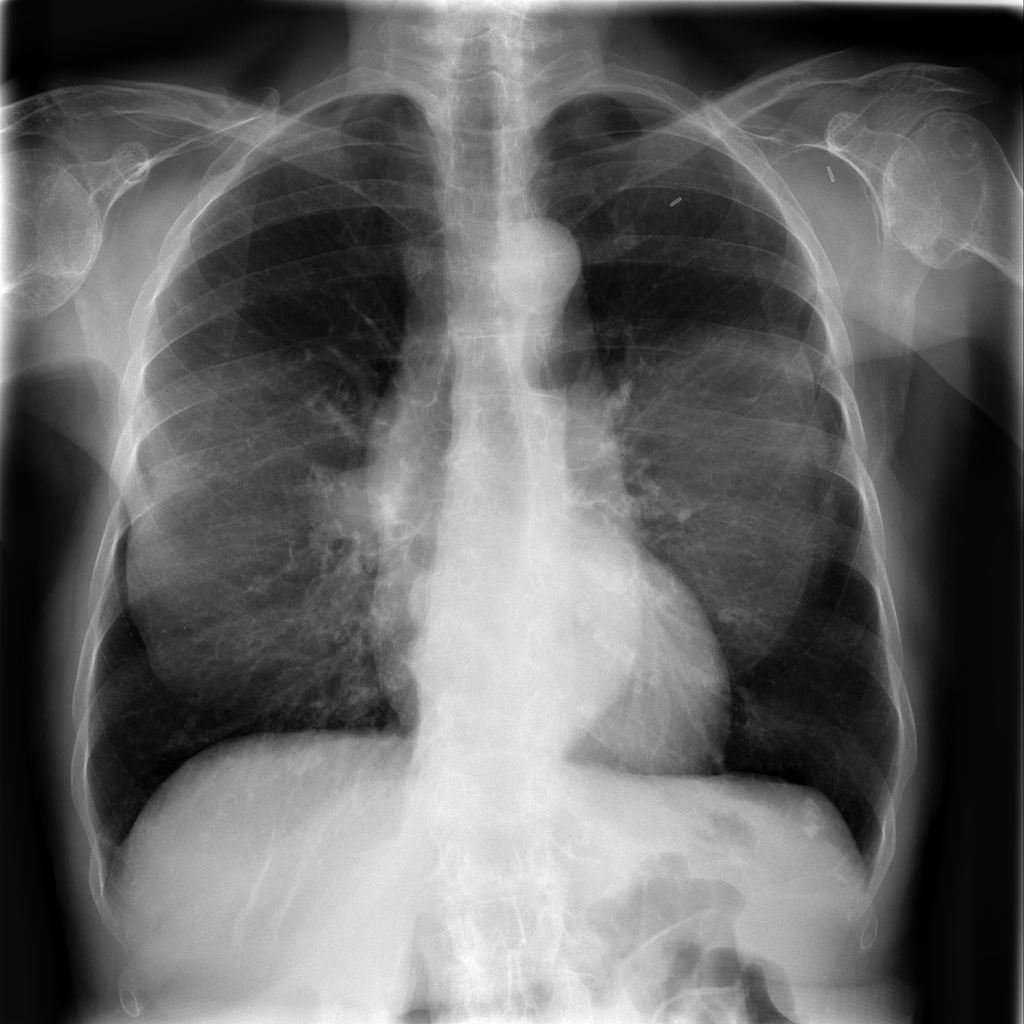

PAT-250B · IMG-000Nodule

PAT-250B · IMG-000

PA